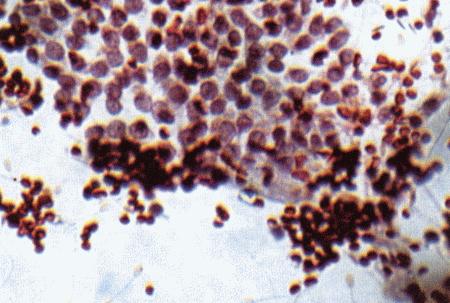

Фиг. 2.2.

Вагинальные выделения кошки (а). Выделения, типичные для фазы эструса. Большая часть клеток представляет собой безъядерные кератинизированные клетки или клетки с пикнотическим ядром. Присутствуют промежуточные клетки (b). Выделения, характерные для метэструса, — «течки», иногда наблюдаемой у кошек в конце эструса. Присутствуют поверхностные и промежуточные клетки, повышено содержание лейкоцитов. Этот короткий метэструс наблюдается в течение 24–48 часов (см. Приложение)